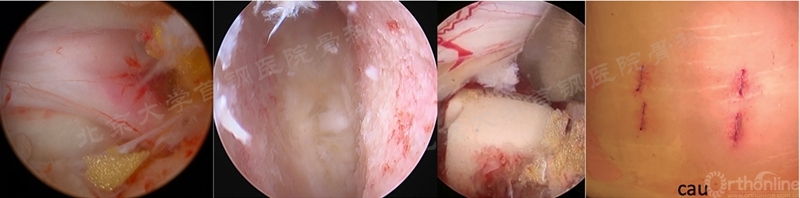

目前报道的UBE/BESS主流融合术式即为(U)BE-TLIF,部分学者将其简称为ULIF,但这一名称国内很多学者认为其可能会引起歧义,也不能很好地表达双通道下融合的特性,所有将其称为BE-LIF或许更好。Dong Hwa Heo、Ju Eun Kim、Man Kyu Park等早期的报道以及我国多数手术演示的BE-LIF都是采用完全切除同侧关节突关节的这种方式(图9),而且作者们一致提出此术式类似MIS-TLIF,故将此融合方式归为TLIF。

图9 多位学者报道的BE-TLIF术中及术后伤口照片(来源于多个文献中的图片)